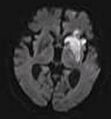

The most common application of conventional DWI (without DTI) is in acute brain ischemia. DWI directly visualizes the ischemic necrosis in cerebral infarction in the form of a cytotoxic edema,[38] appearing as a high DWI signal within minutes of arterial occlusion.[39] With perfusion MRI detecting both the infarcted core and the salvageable penumbra, the latter can be quantified by DWI and perfusion MRI.[40]

DWI showing necrosis (shown as brighter) in a cerebral infarction